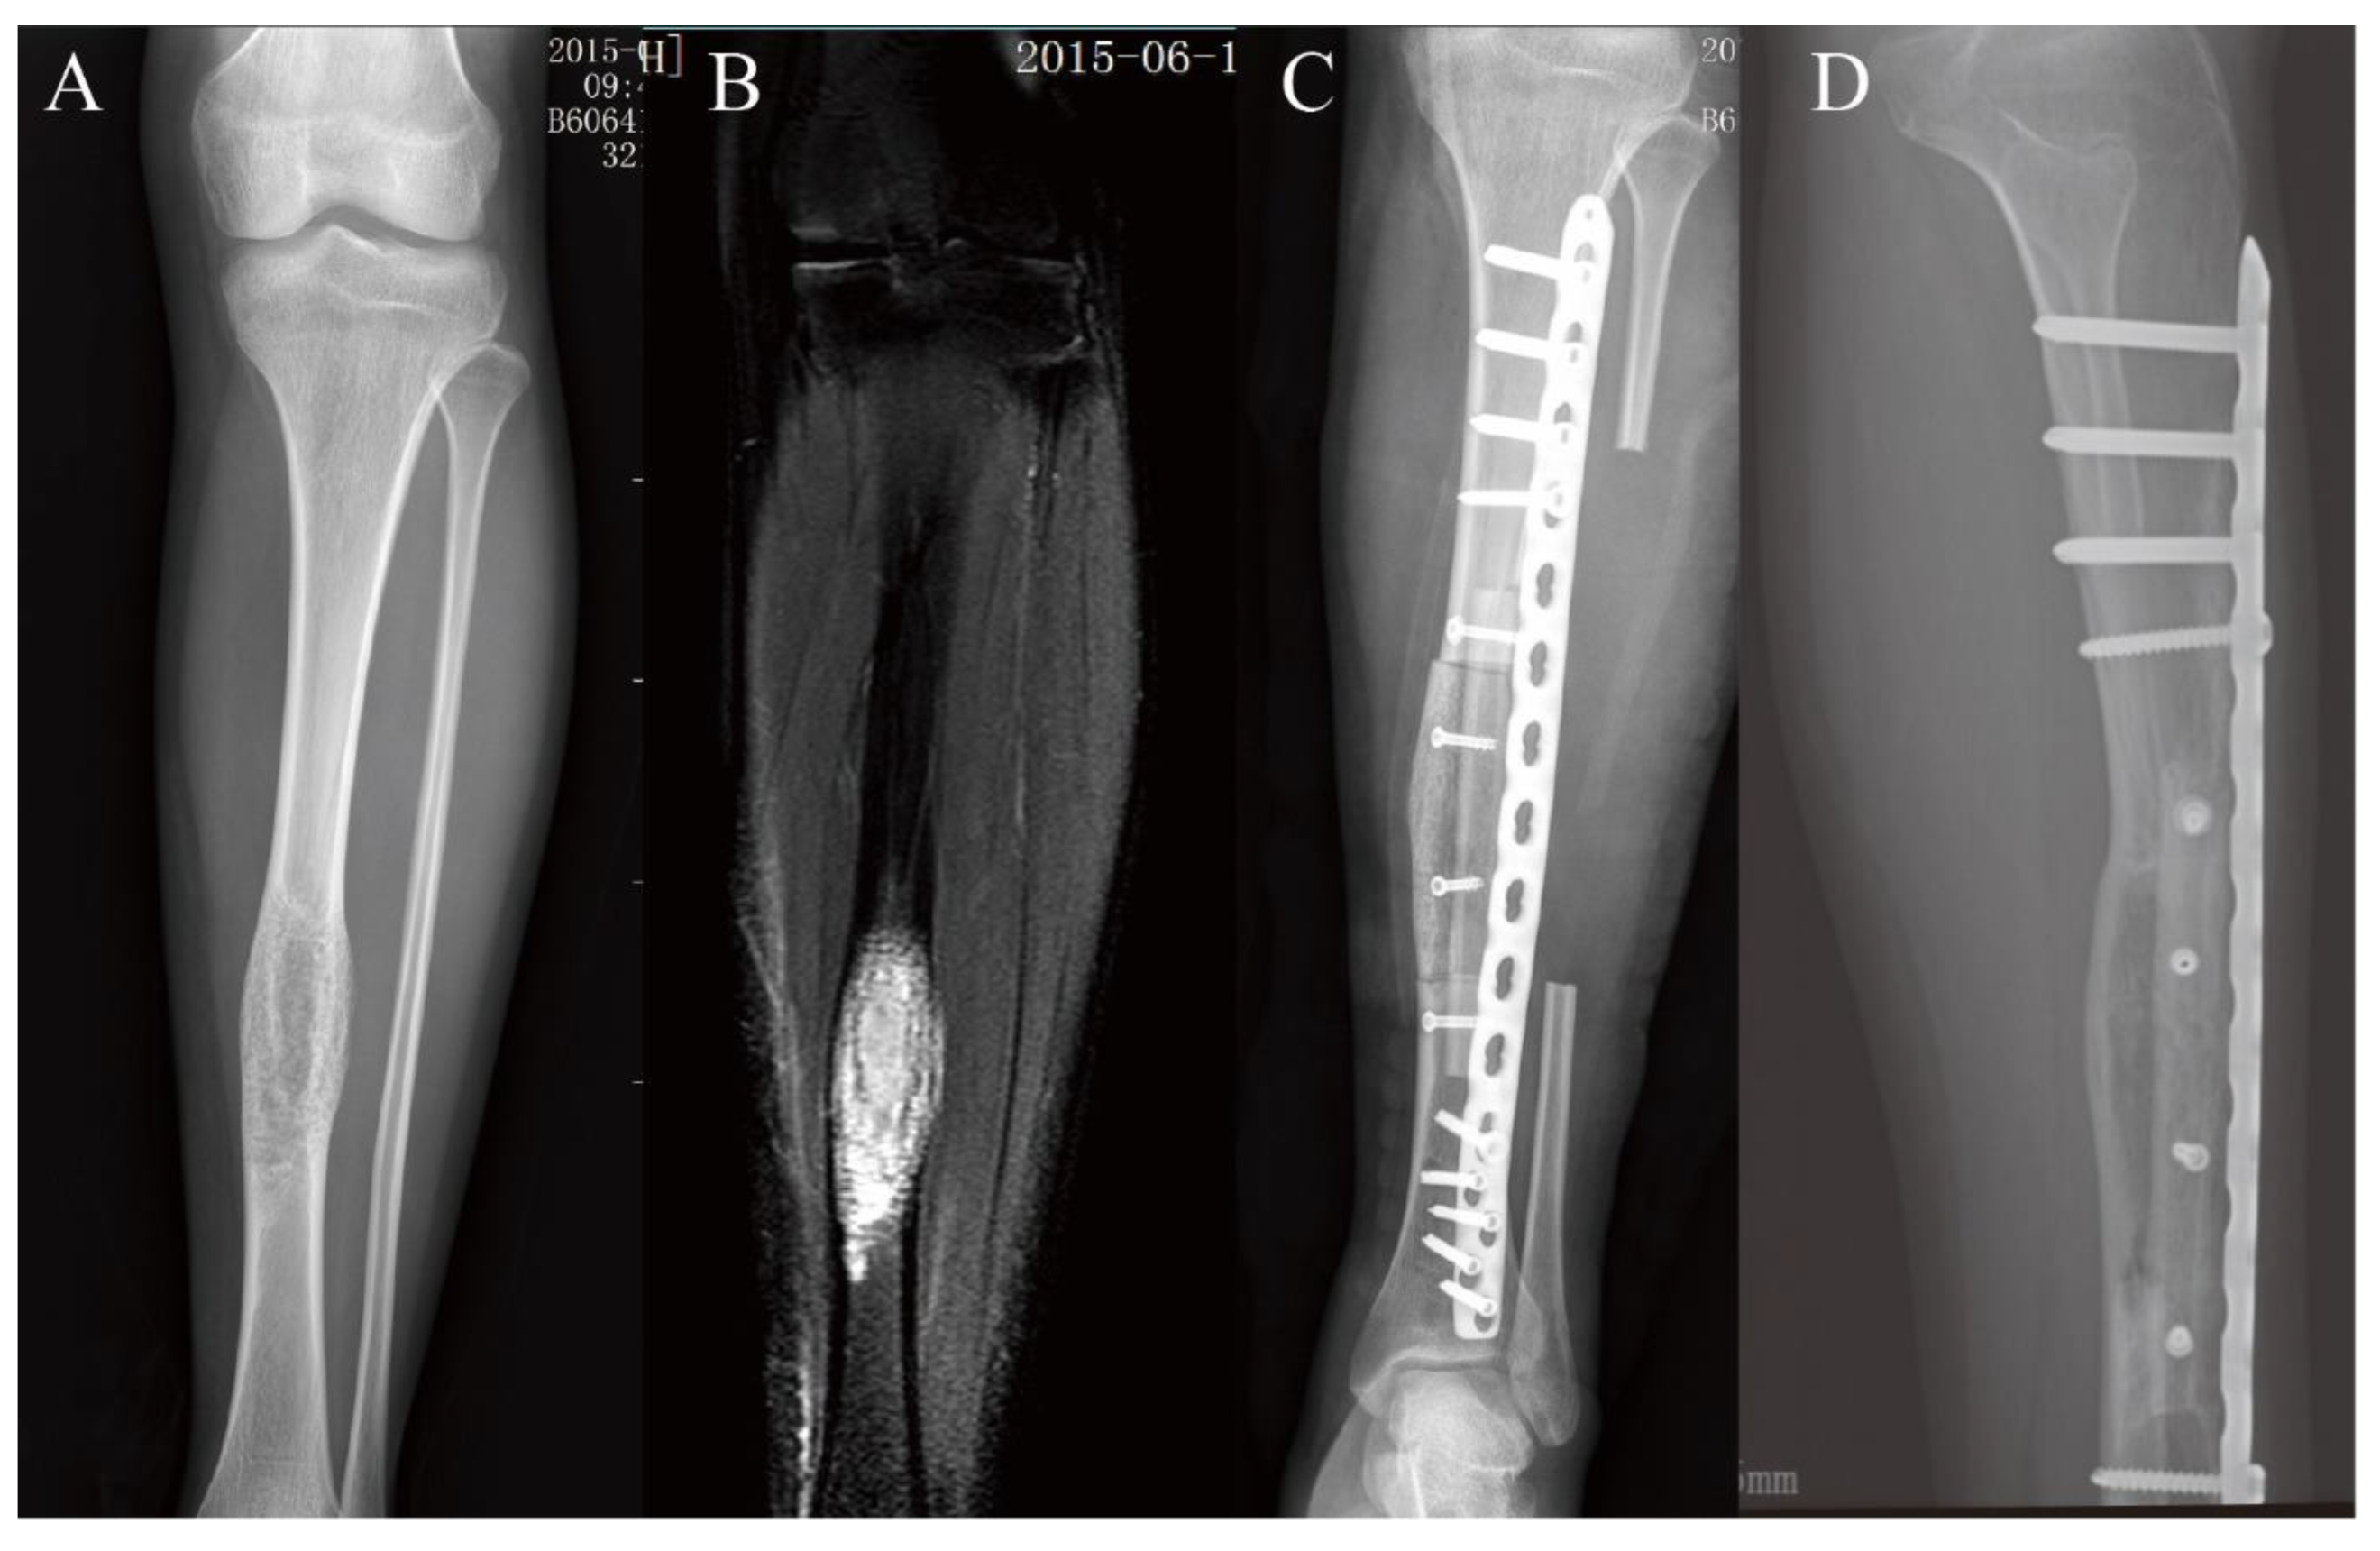

2.2. Surgical Technique

3.2. Lower Extremity Reconstruction Results